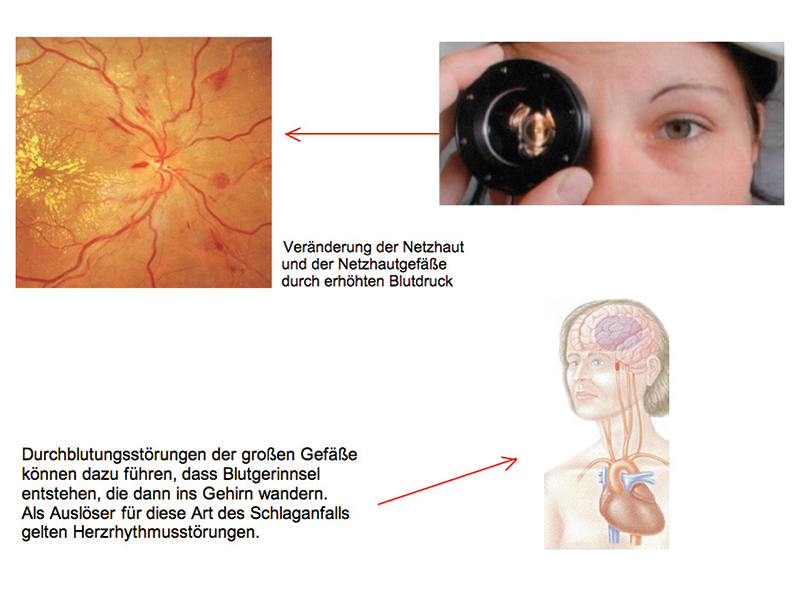

Schlaganfallprophylaxe mit der Kontaktglas-Dynamometrie

11,4% aller Todesfälle in Deutschland sind eine Folge von Schlaganfällen. Begünstigt werden Schlaganfälle durch Risikofaktoren, wie zum Beispiel Rauchen, Bluthochdruck, zu kalorienreiches Essen, übermäßiger Alkoholkonsum oder Bewegungsarmut. Wenn man alle Risikofaktoren frühzeitig erkennen würde, dann ließen sich 40-50% aller Schlaganfälle verhindern.

Das Auge als Fenster zum Hirn

Unzweifelhaft kann chronisch erhöhter Blutdruck zum Schlaganfall führen. Um diesen Risikofaktor möglichst früh zu erkennen, genügt es manchmal nicht, den Druck lediglich am Oberarm zu messen. Denn das Gefäßsystem ist weit verästelt und Verengungen der Adern können zu lokal erhöhten Drücken führen. Doch wie kann direkt in Organen ohne einen Eingriff gemessen werden? Am Kopf zumindest befindet sich ein naturgegebenes Fenster: das Auge. In seiner Netzhaut liegen zahlreiche Blutgefäße, die der Augenarzt auf krankhafte Veränderungen hin untersuchen kann. Um den systolischen und diastolischen Druck in den Gefäßen zu messen, bedienen wir uns einer eleganten, schnellen und nicht-invasiven Methode: der Kontaktglas-Dynamometrie.

Man unterscheidet drei Typen von Gefährdungen:

Für Schlaganfälle der kleinen Gefäße ist vor allem ein zu hoher Blutdruck verantwortlich.

Bei der dritten Gruppe der Schlaganfallpatienten kommt es zu einer Verengung der Halsschlagader. Zu dieser Risikogruppe gehören Raucher und Menschen mit hohen Blutfettwerten.

Abbildung: Hochgradige Verengung der Arteria carotis interna

Schlaganfallprophylaxe